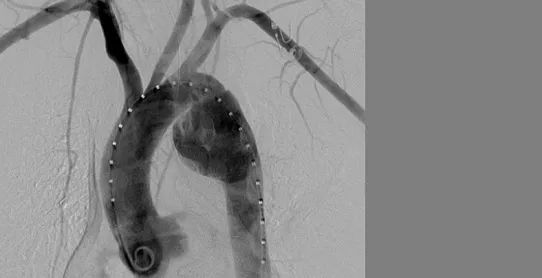

心脏彩超、X线平片,有助及早识破主动脉夹层,增强CT、MRI均可做出明确诊断。